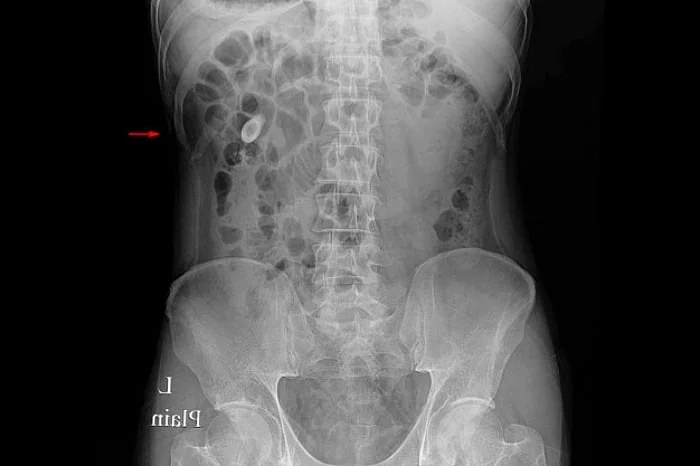

سنگ کلیه بیماری بسیار دردناکی است که در مردان بیش از زنان است و خود را با درد در ناحیه پهلو نشان می دهد و می تواند سبب کاهش یا توقف ادرار در افراد شود.

سنگ های کلیه از باقیمانده املاح و مواد شیمیایی که فرد به همراه مواد غذایی یا مایعات مصرف می کند در مثانه یا کلیه ایجاد می شود.

انواع سنگ کلیه

سنگ های کلیه گونه های مختلفی دارند از جمله:

• سنگ های اگزالات کلسیم

• فسفات کلسیم

• سنگ استرویت (struvite)

• اسید اوریک و سیستین